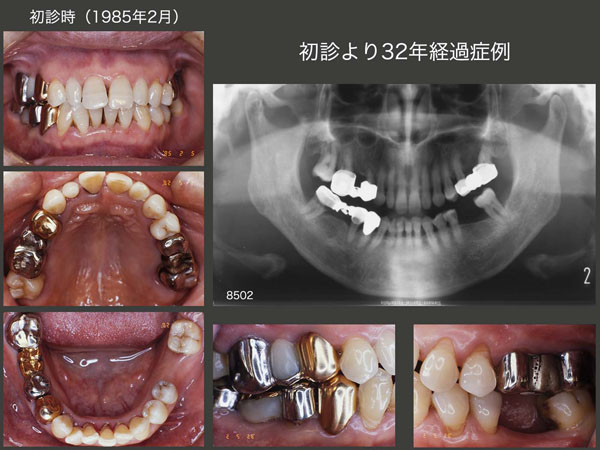

1.初診より32年経過症例

初診は1985年2月,49歳女性.東京歯科大学千葉病院勤務の時の患者さんであり,私は歯科医師になって5年目.全顎にわたり不適合な補綴装置が装着されており,歯周病も進行していた.歯周基本治療,歯周外科処置を施したのちに固定式のブリッジを製作した.

1986年7月,初診から1年5ヵ月後の治療終了時の状態.(スライド中段は,86年4月,ブリッジ装着前の支台歯の状態.)当時の自分は,これが精一杯の治療で,可撤式のブリッジ(コーヌス義歯)は考えていなかった.また,当時歯内療法は保存科で行って貰ったが,ここまで抜髄する必要があったのか疑問である.もう少し,有髄歯に拘って貰いたいと思うが,当時私を含めて,そこまでの考えには及んでいなかった.